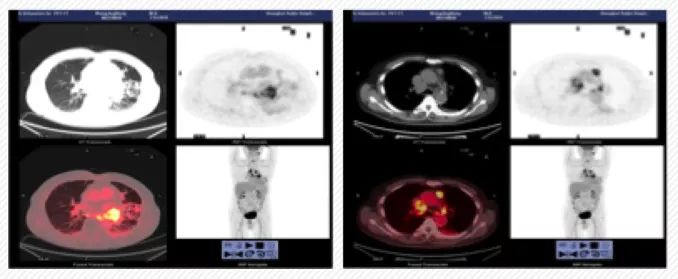

6. PET/CT检查示:左肺门代谢增高团块影,考虑恶性病变,下叶局部胸膜增厚,伴代谢增高,转移性病变可能,双肺门代谢增高,考虑转移性病变;右锁骨上、下,纵隔多发淋巴结肿大伴代谢增高,考虑转移性病变。

图2. PET/CT检查

11. 复查评估:9月23日复查PET/CT显示左肺门高代谢团块,考虑恶性病变,与2019年7月24日全身PET/CT比较,大小相仿,代谢增高;双侧胸腔见少量积液;双侧背部胸膜增厚;纵膈、双肺门及右锁骨上高代谢肿大淋巴结,与前片比较,大小相仿,代谢增高;左肺上叶结节,边缘毛刺,代谢增高;右肺上叶磨玻璃结节,代谢不高;双肺肺气肿,双肺下叶及右肺中叶间质性改变,评估结果为SD。

图3. 2019年9月23日PET/CT